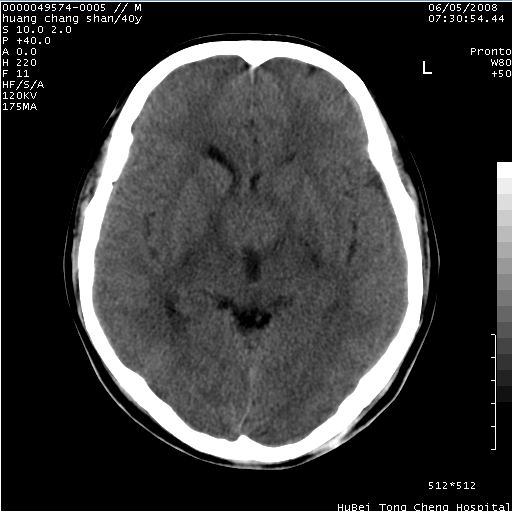

患者 m,40y。头痛,视力模糊,多饮多尿,性欲减退半年余。

行ct平扫+增强,图象如下:

肿瘤强化明显、鞍部骨质结构未见增大、破坏,考虑脑膜瘤可能性大

鞍背无破坏和明显受压,病变明显均匀强化,边界清晰。鞍上区脑膜瘤可能性大,不除外生殖细胞瘤。

平扫病灶呈等密度,增强后强化明显,均匀一致,结合病史首先考虑:垂体瘤。脑膜瘤不支持,因为脑膜瘤平扫多为实性呈均匀高密度影像,内分泌症状多不明显,垂体内分泌素测定正常。

鞍上池肿瘤,鞍背及垂体窝形态变化不明显,病灶强化密度均匀且高度强化,考虑实性颅咽管瘤、生殖细胞瘤及脑膜瘤可能。

结合临床考虑鞍上生殖细胞瘤可能性大于脑膜瘤(增强未见脑膜围征),建议结合冠状位扫描看病灶起源及垂体窝、鞍底情况。垂体窝内未见明显软组织密度影,垂体窝未见扩大,暂不考虑垂体瘤;病灶较大,未见囊变及钙化,颅咽管瘤不支持。期待结果!

1、头痛,视力模糊,多饮多尿,性欲减退半年余,提示:肿瘤为功能性肿瘤。

2、ct表现:肿瘤呈类圆形,均匀略高密度,无囊变,无钙化。侧脑室有扩大。

3、首先考虑:功能性垂体大腺瘤。

4、鉴别诊断:脑膜瘤,瘤体内点状钙化最具特征性,常位于鞍结节。颅咽管瘤,蛋壳样钙化,常有囊变。动脉瘤,位于鞍旁,强化与动脉一致。有时尚需与发生于鞍区的生殖细胞瘤鉴别,生殖细胞瘤钙化亦较常见。

5、友情提示:下回发现鞍区占位性病变,最好加扫冠状位,了解肿瘤与蝶鞍的关系及蝶鞍骨质的改变。